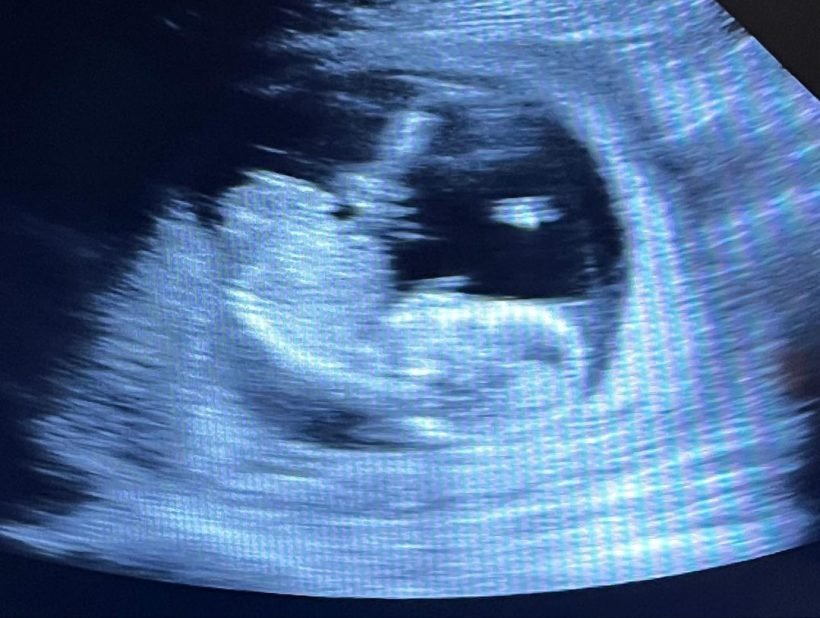

สำหรับ ‘คุณนนท์ ร้อยเอก ทศสีห์ โควสุรัตน์’ ลูกชายของ ‘คุณสิทธิชัย โควสุรัตน์’ อดีตรัฐมนตรีช่วยว่าการกระทรวงมหาดไทย ที่มาพร้อม ‘คุณเตย ปรีดิ์รติ ภิรมย์ภักดี’ ทายาท ภิรมย์ภักดี ล่าสุดทั้งคู่โพสต์ภาพที่ทุกคนรอคอยพร้อมแคปชั่นว่า “Happy 2nd anniversary jaa Here we grow again! We’re thrilled to share the news that Preen is being promoted to big sister. Baby #2 is on the way!!!”